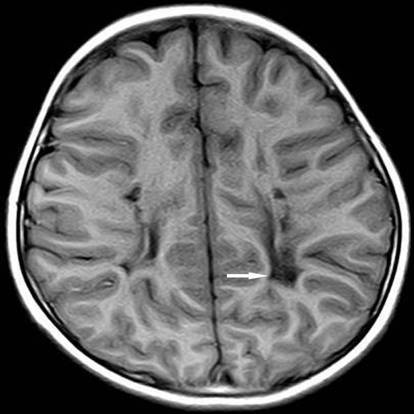

2、痉挛型脑性瘫痪 是最典型和常见的类型医|学教育网整理。主要表现以双下肢为主的痉挛性截瘫获四肢瘫痪。患儿行走、站立困难,走路足尖着地呈剪刀步态。肌张力明显增高,腱反射亢进,可有病理反射。常伴有语言及智能障碍。

4、手足徐动型脑性瘫痪 多由核黄疸、新生儿窒息引起的基底核损害而发病。患儿表现为面、舌、唇及躯干肢体的舞蹈样或徐动样动作。伴有运动障碍和肌张力增高。